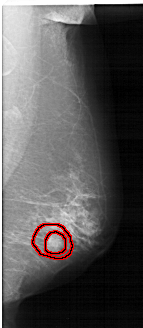

RIGHT_MLO LINES 6226 PIXELS_PER_LINE 2701 BITS_PER_PIXEL 12 RESOLUTION 43.5 OVERLAY

FILE: A_1252_1.RIGHT_MLO.OVERLAY

TOTAL_ABNORMALITIES 1

ABNORMALITY 1

LESION_TYPE CALCIFICATION TYPE PLEOMORPHIC DISTRIBUTION CLUSTERED

LESION_TYPE MASS SHAPE IRREGULAR MARGINS SPICULATED

ASSESSMENT 5

SUBTLETY 4

PATHOLOGY MALIGNANT

TOTAL_OUTLINES 2

BOUNDARY

CORE